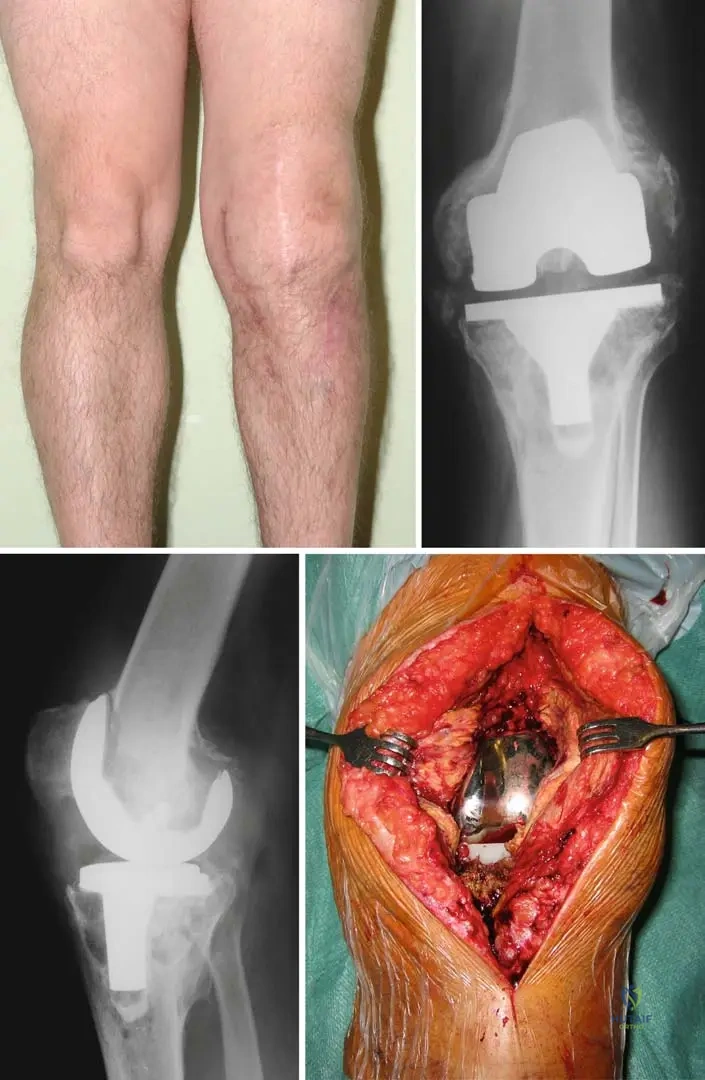

A 60-year-old patient presents with chronic hip pain. Radiographs show significant lytic destruction in the proximal femur with concentric narrowing of the femoral neck, as depicted in the image. This finding is characteristic of which aspect of Gorham's disease?

View Answer & Explanation

Correct Answer: C

Rationale: The image (Fig. 8.57) shows "Lytic destruction in the proximal femur with concentric narrowing of the femoral neck," which is a direct visual representation of the "massive, progressive osteolytic changes" that define Gorham's disease. Main Distractor: Option B, malignant bone tumor infiltration, is incorrect. While it can cause lytic lesions, Gorham's disease is a benign vascular process, and the pathology explicitly states no cytological atypia, ruling out malignancy.

A 45-year-old male presents with a "vanishing bone" phenomenon in his left leg. An AP radiograph of the left femur, as shown, demonstrates complete resorption of the diaphysis. This radiographic appearance is a hallmark of Gorham's disease and signifies what?

Correct Answer: B

Rationale: The image (Fig. 8.62) shows "complete resorption of diaphysis," which is an extreme manifestation of the "massive, progressive osteolytic changes" characteristic of Gorham's disease. This represents extensive and advanced destruction. Main Distractor: Option D, early stages of bone healing, is incorrect. The image clearly shows severe bone loss, which is the opposite of early healing. While sclerotic bone may accompany healing later, complete resorption is a destructive phase.